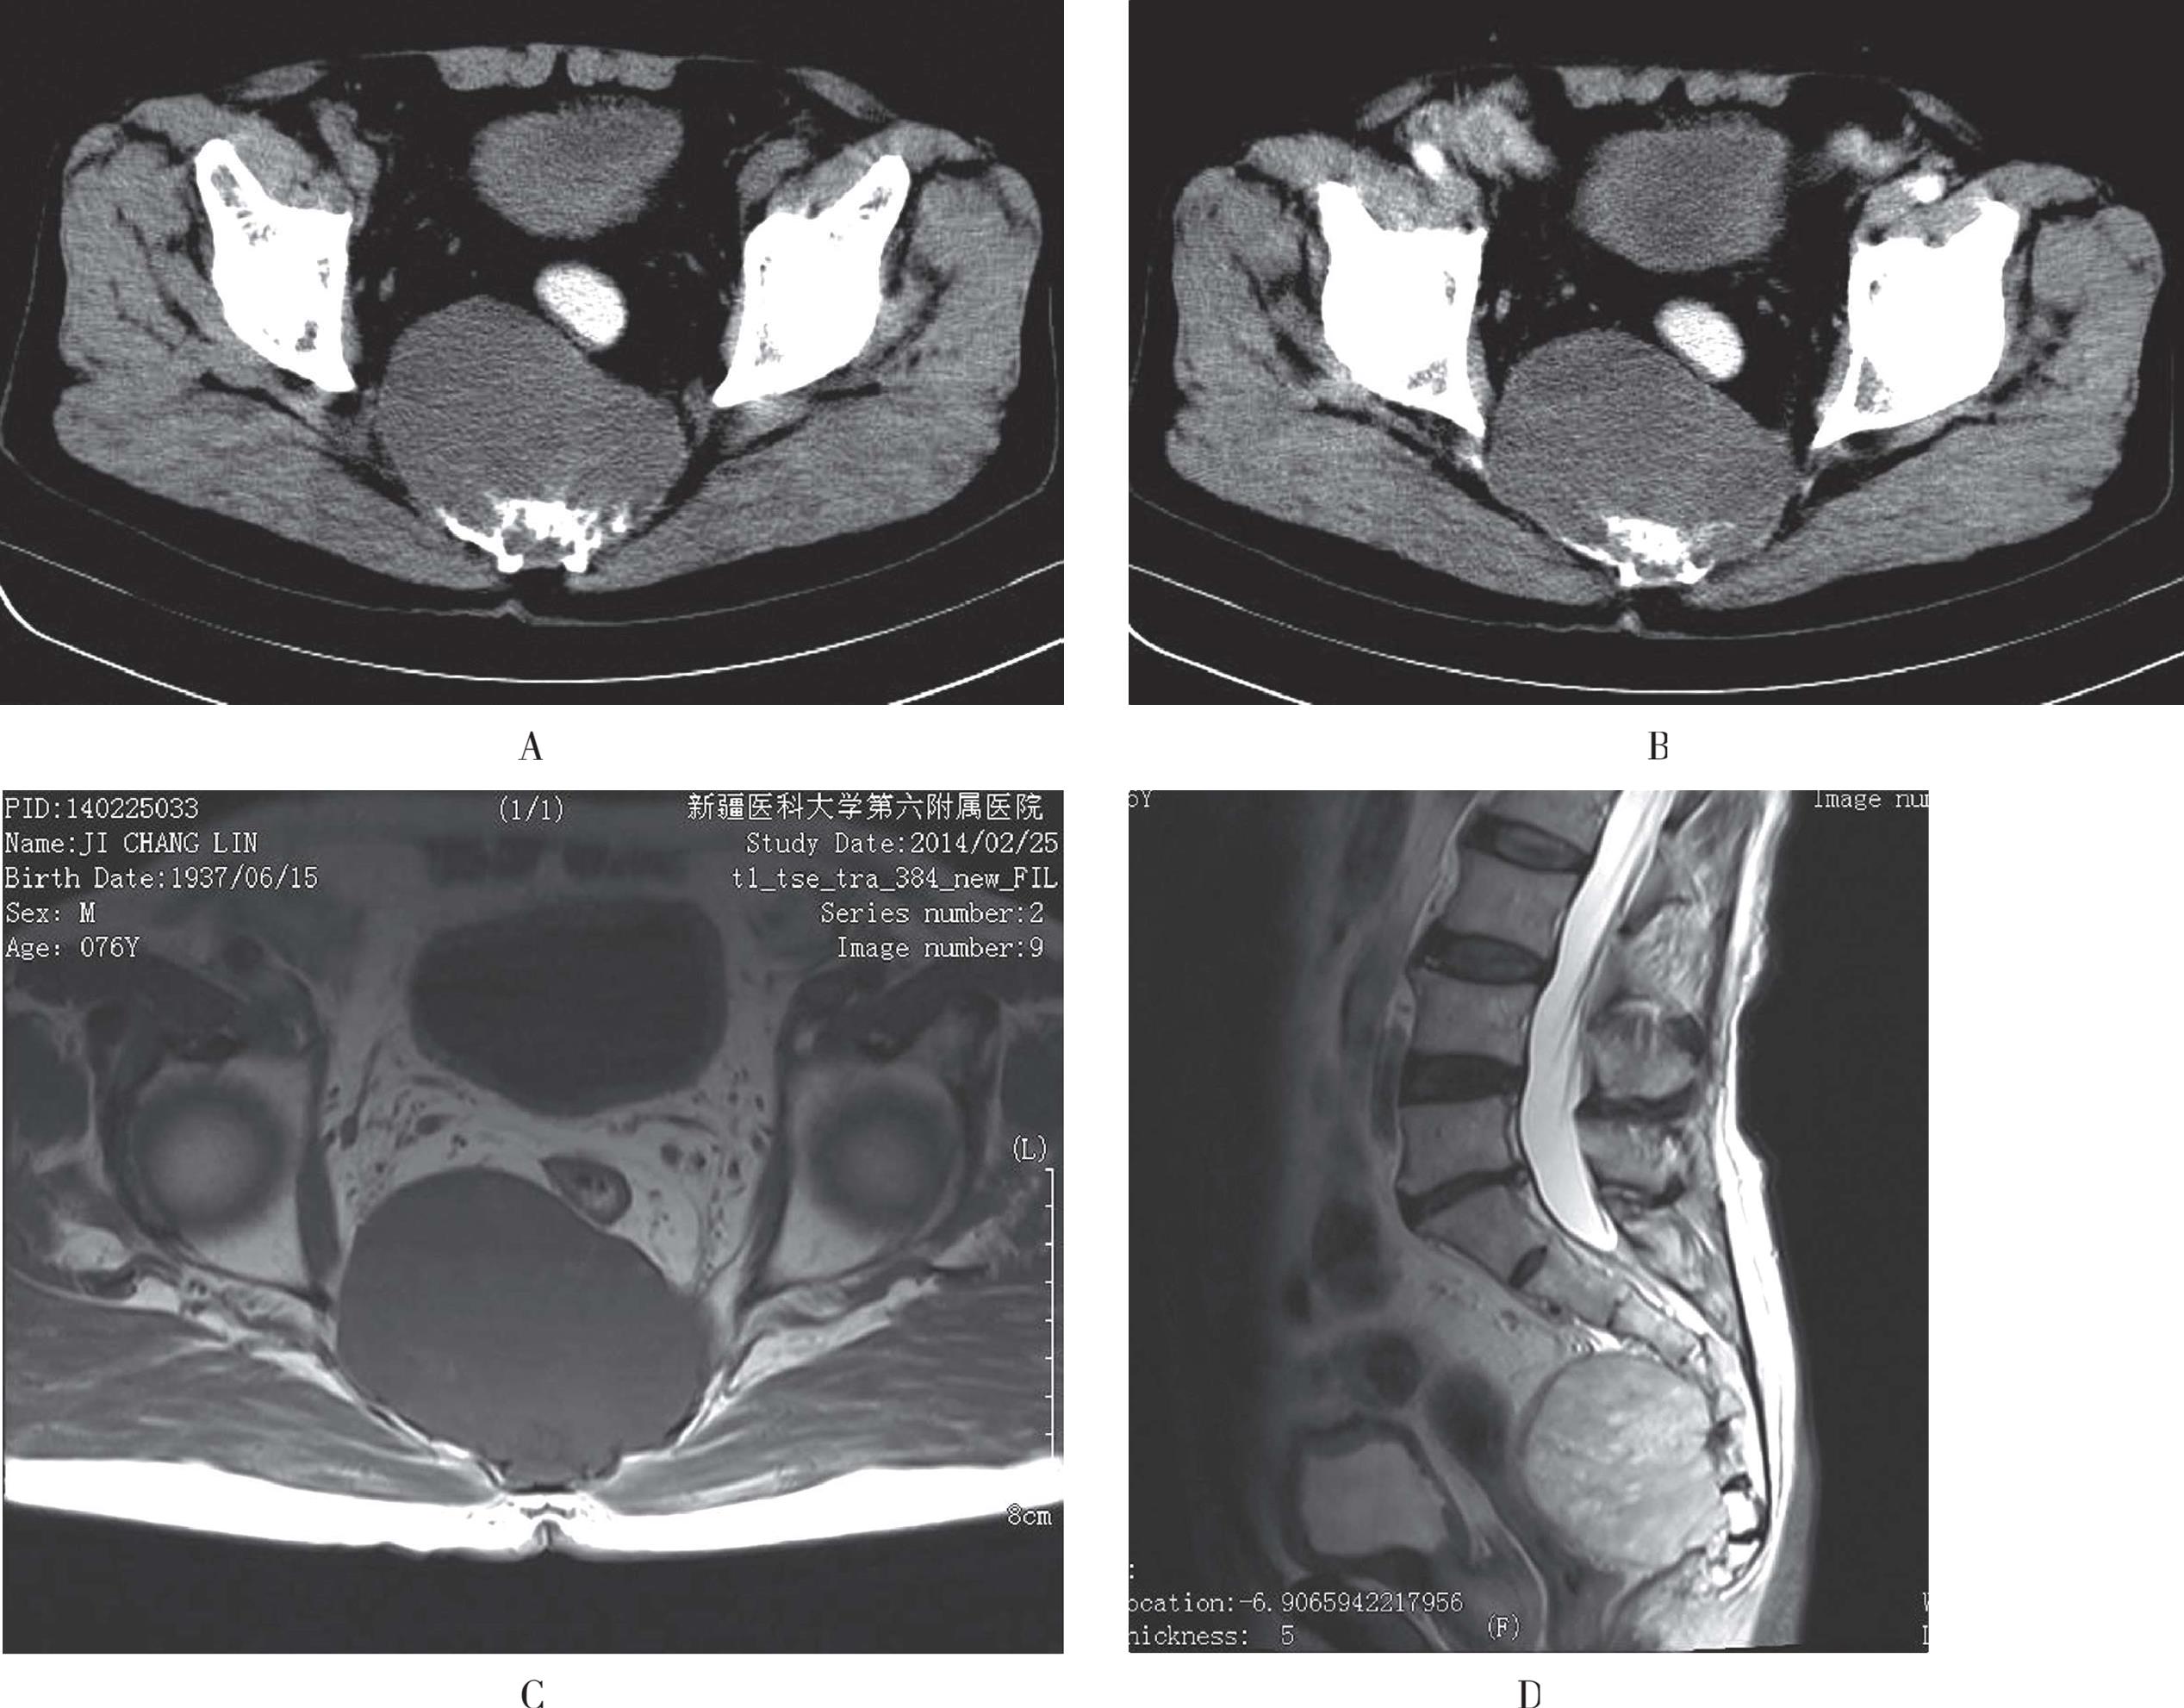

A、B. CT示骨盆诸骨广泛、较大骨质破坏区,其内未见骨小梁,临近骨皮质变薄;C. T1WI双层股骨头、颈及髋臼见多发斑片状、结节状低信号,局部骨皮质欠连续;D、E. T2WI双侧股骨头、颈及髋臼、耻骨内多发病灶信号增高,T2-tirm上病变呈高信号

图3-52 骨髓瘤的影像学表现

CT常常显示大量、多发、巨大的骨内破坏灶,破坏灶内骨小梁消失,甚至骨皮质破坏;骨髓瘤造成的骨破坏以髓内松质骨为主,骨皮质破坏出现较晚。一些X线片仅表现为骨质疏松,CT可显示细微的骨质破坏,在出现脊柱压缩性骨折时,CT可显示椎管内脊髓及神经根有无受压以及椎体周围有无软组织肿块等。CT检查的优点有:①能证实X线检查结果;②能更好地确定病变范围,尤其是髓外浸润病灶的范围;③能发现X线检查阴性的多发性骨髓瘤病灶,尤其是病变早期(图3-52A、图3-52B)。

MRI是检测骨髓瘤最敏感的影像学检查方法,它可在骨质破坏之前显示骨髓内病灶的浸润,以T1WI和STIR显示较好,MR检查的价值还在于检出非分泌型的骨髓瘤,在穿刺出现假阴性结果时指导穿刺部位,并可判断椎体压缩的危险性以及有无脊髓、神经根的压迫。骨髓内仅5%~20%异型浆细胞浸润时,脊髓的MRI信号正常,骨髓内大量肿瘤细胞浸润时,正常骨髓组织被广泛代替,脊髓呈现为T1WI弥漫性均匀低信号,T2WI信号增高;肿瘤细胞聚集成瘤结节时骨髓在T1WI表现为斑片状或结节状低信号,T2WI信号增高,病灶具有多发性,多不对称,骨髓瘤还可表现为“盐-胡椒状”,为肿瘤出现弥漫性浸润同时伴有局部瘤细胞聚集成团,在脂肪抑制T2WI显示最为明显。增强后骨髓瘤病灶呈弥漫性、不均匀片状、结节状强化(图3-52C至图3-52E)。